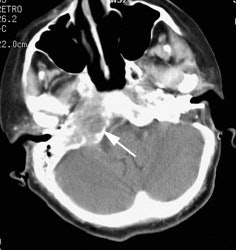

Metastatic head and neck cancer with secondary lung malignancy: The patient shown below had a history of head and neck cancer. The PET scan demonstrated a metastatic lesion to the right temporal bone. Also noted was intense uptake in the right lung apex(black arrow below right)- on CT this was felt to represent scarring (black arrowhead). FDG uptake is highly suggestive of a separate primary lung cancer. |